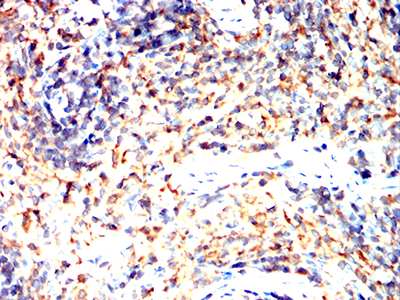

Immunohistochemical analysis of paraffin-embedded Rat spleen using CD163 mouse mAb with DAB staining.

-

Immunohistochemical analysis of paraffin-embedded Rabbit spleen using CD163 mouse mAb with DAB staining.